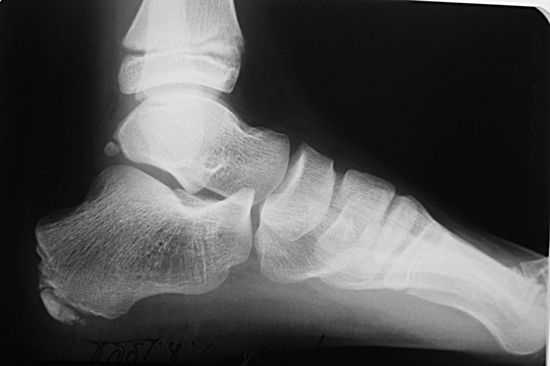

Диагноз выставляется ортопедом с учетом анамнеза, клинической картины и рентгенологических признаков. Наиболее информативен снимок в боковой проекции. Рентгенография пяточной кости на 1 стадии заболевания свидетельствует об уплотнении бугра, расширении щели между бугром и собственно пяточной костью. Выявляется также пятнистость и неравномерность структуры ядра окостенения, участки разрыхления кости и коркового вещества и смещенные в сторону от центра секвестроподобные тени. На поздних стадиях на рентгенограммах видны фрагменты бугра, а затем признаки перестройки и формирования нового губчатого вещества кости. В норме пяточный бугор может иметь до четырех ядер окостенения, что часто затрудняет рентгендиагностику. В сомнительных случаях выполняют сравнительную рентгенографию обеих пяточных костей либо направляют пациентов на КТ пяточной кости или МРТ пяточной кости.

Рентгенография может показать:

- пятна в районе паточной кости и отсутствие однородности затемнения пяточного бугра;

- отсутствие однородности структуры ядра окостенения;

- возможные места разрыхления пяточной кости;

- процесс формирования обновленного губчатого вещества в отдельных участках кости пятки;

- при остром протекании заболевания можно увидеть отделение осколков и образование пространства между костью пятки и апофизом.

Поскольку пяточный бугор часто имеет около четырех эпицентров окостенения, этот факт иногда затрудняет диагностику болезни Шинца. Для формирования правильного диагноза ортопед может назначить сравнительную рентгенодиагностику. Если эта процедура не дает полной картины для вынесения диагноза, пациента отправляют на КТ или МРТ пятки.